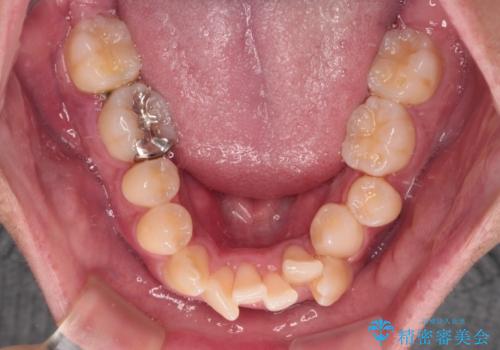

- 前歯のデコボコや八重歯を気にして来院された患者様です。

他院でワイヤー矯正を行うつもりでいらっしゃったそうですが、通院が難しくなったとのことで当院での治療を希望されて来院されました。

上下ともに歯列幅が狭く、その影響でデコボコになっていたため、ワイヤー装置を用いて歯列を側方に拡大しながら、デコボコを解消していくこととしました。